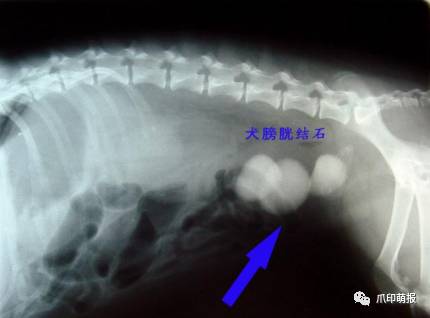

引起尿道阻塞的原因有感染、发炎、结石、肿瘤等原因,如果是部份阻塞,当膀胱内尿液的压力大于阻力时,尿液及会不自主的流出,引起尿*禁失**。

膀胱是储存尿液的位置,在膀胱发炎或结石的时候,因为膀胱壁的过度刺激,引起膀胱平滑肌的收缩,造成不定期的排尿,也可能是因为膀胱内壁有肿瘤的生长,引起尿液储存量下降,而引起排尿频率上升。

饲主需要仔细观察小狗排尿时的行为与时间,提供给兽医师完整的讯息,兽医师也会藉由理学检查、神经学检查、腹腔触诊、血液学检查、x光检查、膀胱造影术、尿液分析等方法,详细的评估出漏尿的原因。